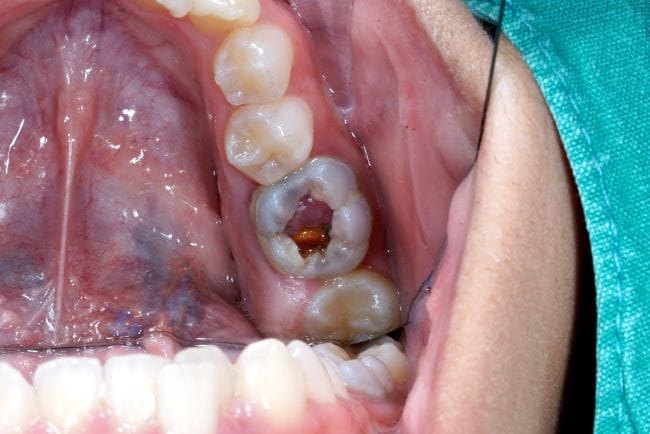

Gigi berlubang tumbuh daging adalah kondisi ketika timbul benjolan berwarna kemerahan yang menyerupai daging pada gigi berlubang. Kondisi yang juga disebut sebagai polip pulpa ini bisa terjadi ketika bagian tengah gigi yang penuh dengan jaringan (pulpa) mengalami infeksi bakteri.

Gigi berlubang tumbuh daging pada dasarnya disebabkan oleh peradangan kronis pada pulpa gigi. Pulpa gigi adalah bagian yang penuh dengan jaringan dan satu-satunya bagian gigi yang mengandung pembuluh darah.

Nah, pasokan darah dan nutrisi di area gigi berlubang juga mengakibatkan pertumbuhan jaringan terus terjadi. Hal inilah yang terlihat sebagai daging berwarna merah muda atau merah di bagian tengah gigi berlubang.

- Timbulnya benjolan lunak berwarna merah muda atau merah di tengah gigi yang berlubang